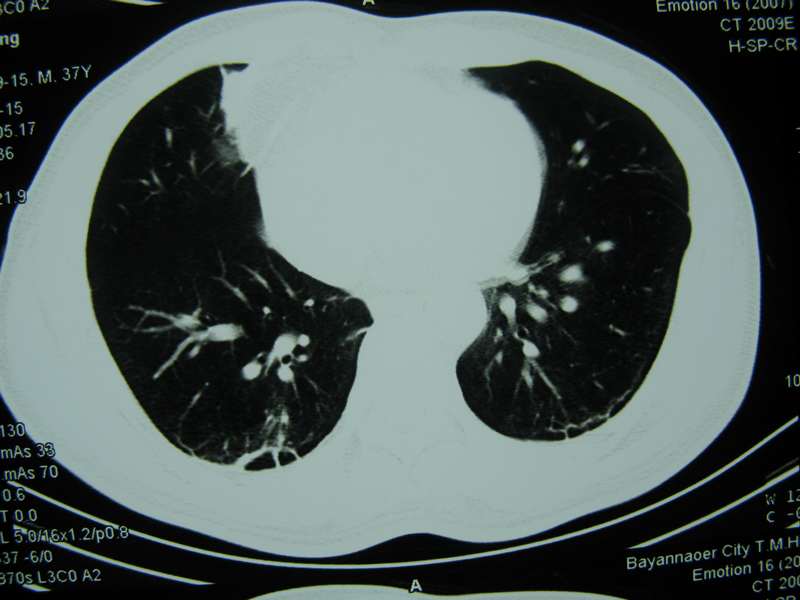

男,37岁,主述胸疼厉害,无咳嗽,无发热,血象也不高,病灶内ct值脂肪密度,右侧胸腔内少量积液,同道们考虑什么?谢谢!

脂肪垫,右下肺感染,少许积液是症状所在

纵膈脂肪堆积,右肺慢性炎症。

两肺下叶基底段纤维灶,右肺下叶基底背侧相应胸膜肥厚,右肺中叶内侧段部分不张。前中下纵隔团块状脂肪影,随访除外胸腺脂肪瘤。

纵膈脂肪堆积,右肺慢性炎症

脂肪垫;右肺慢性炎症。

不除外膈疝。